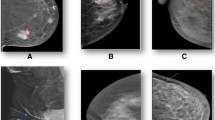

BI-RADS breast density and dense breast volume

The variability in the patterns and amounts of dense tissue portrayed on the mammogram has been characterized by qualitative measures. The Wolfe scale qualitatively assesses breast density by classifying images into one of four patterns (N1 [fatty], P1, P2 [areas of increasing ductal prominence], and DY [significant densities or dysplasia]) on the basis of quantity and distribution of breast density [21]. The BI-RADS density qualitative assessment is similar to the Wolfe scale in that it incorporates the quantity, distribution, and texture of breast density. New automated commercial technologies are available to quantify breast density volume using methods such as VolparaTM and QuantraTM. Texture features or parenchymal complexity has been evaluated on film-screen mammography examinations and shown to be independent of percentage breast density and relative amounts of fibroglandular tissue [22, 23]. Winkel et al. [22] showed that the discriminatory accuracy was highest when a combination of three methods of assessing relative amounts of density and texture on film-screen mammography examinations were combined. Automated evaluation of textural features or parenchymal complexity of breast density is under investigation for digital images, with researchers in several studies reporting features as independent predictors of breast cancer risk [24,25,26]. Our results extend the literature by showing that an automated quantitative breast density measure (dense breast volume) available in clinical practice combined with a qualitative measure that incorporates the quantity, distribution, and texture of breast density (BI-RADS breast density) improves the classification of women with dense breasts at high breast cancer risk.